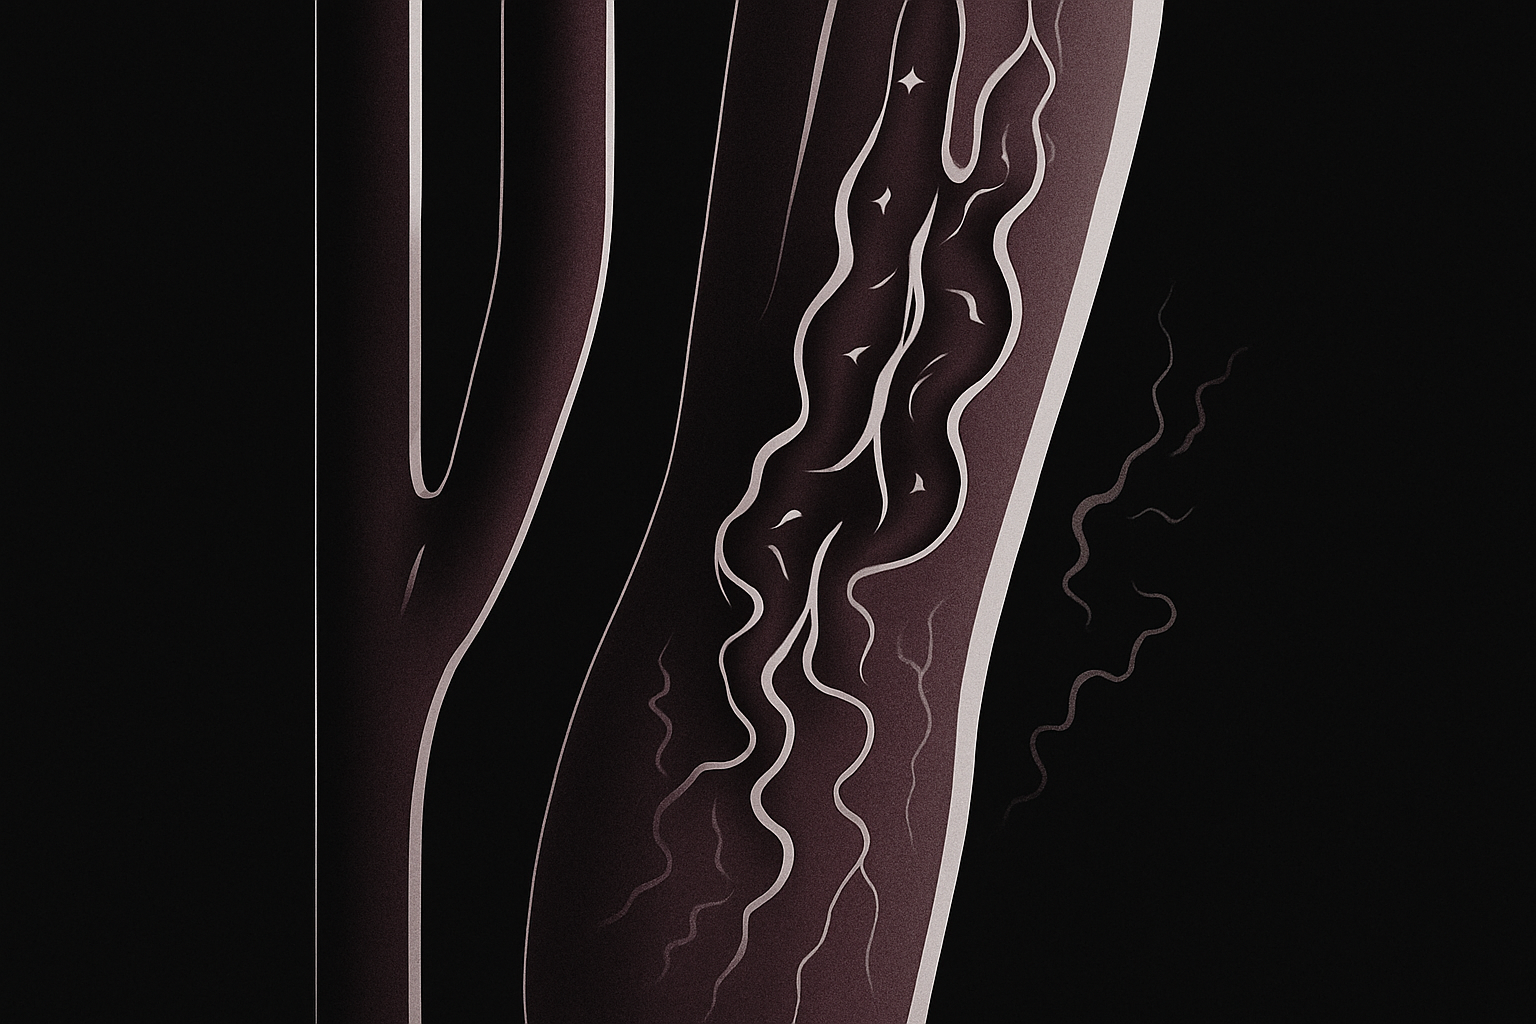

3. Tratamento endovascular (stent de carótida)

- Técnica menos invasiva, realizada por dentro dos vasos.

- Através de um cateter introduzido pela virilha ou braço, o médico coloca um stent (prótese metálica em forma de mola) dentro da artéria, expandindo o canal e mantendo o fluxo sanguíneo aberto.

Geralmente indicada em pacientes com maior risco para cirurgia aberta ou com anatomia favorável.